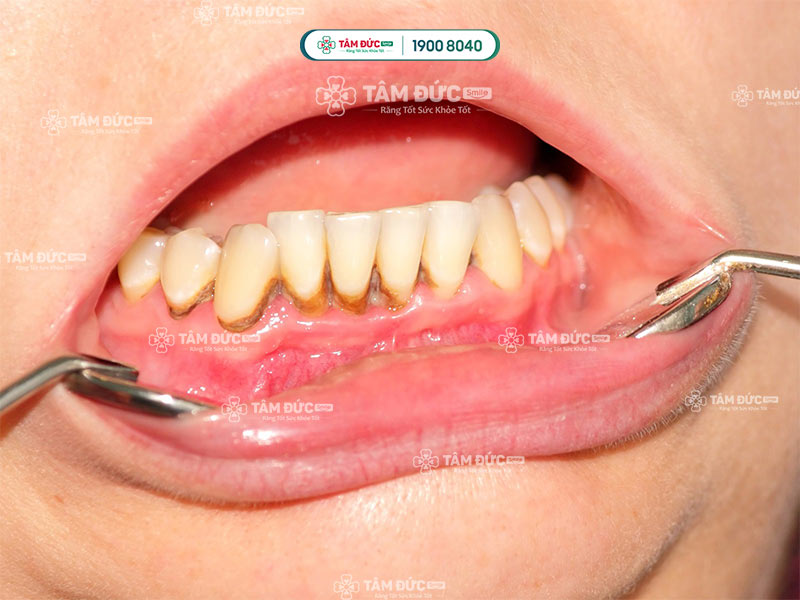

Cao răng tích tụ lâu ngày dẫn đến sâu viêm

Cao răng làm hỏng răng nhanh chóng

Vôi răng gây nên mùi hôi khó chịu

Cận cảnh cạo vôi răng cho khách hàng 35 năm chưa từng cạo vôi răng.